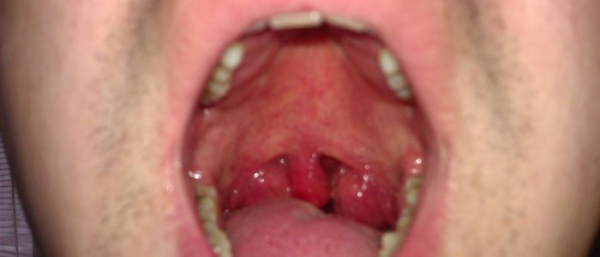

Плоскоклеточная папиллома языка в первый период своего развития не проявляется никакими болезненными симптомами. Пациент может чувствовать болевые ощущений особенно после того, как травмирует папиллому. Зачастую они выглядят как бородавки белого или телесного цвета. Пациенты замечают неприятный запах изо рта, маленькие язвочки в ротовой полости, жжение и зуд пораженного участка языка, проблемы с речью.

Образования в ротовой полости

В полости рта появляется папиллома, похожая на бородавку или тонкая на ножке. Пациент жалуется на проблемы с речью и дикцией, плохой запах изо рта, болезненные ощущения во время речи и еды. Отмечается так же появление маленьких язвочек. Встречается обильное слюноотделение. Все вышеуказанные плоскоклеточные папилломы легко диагностировать, так как они находятся на виду.